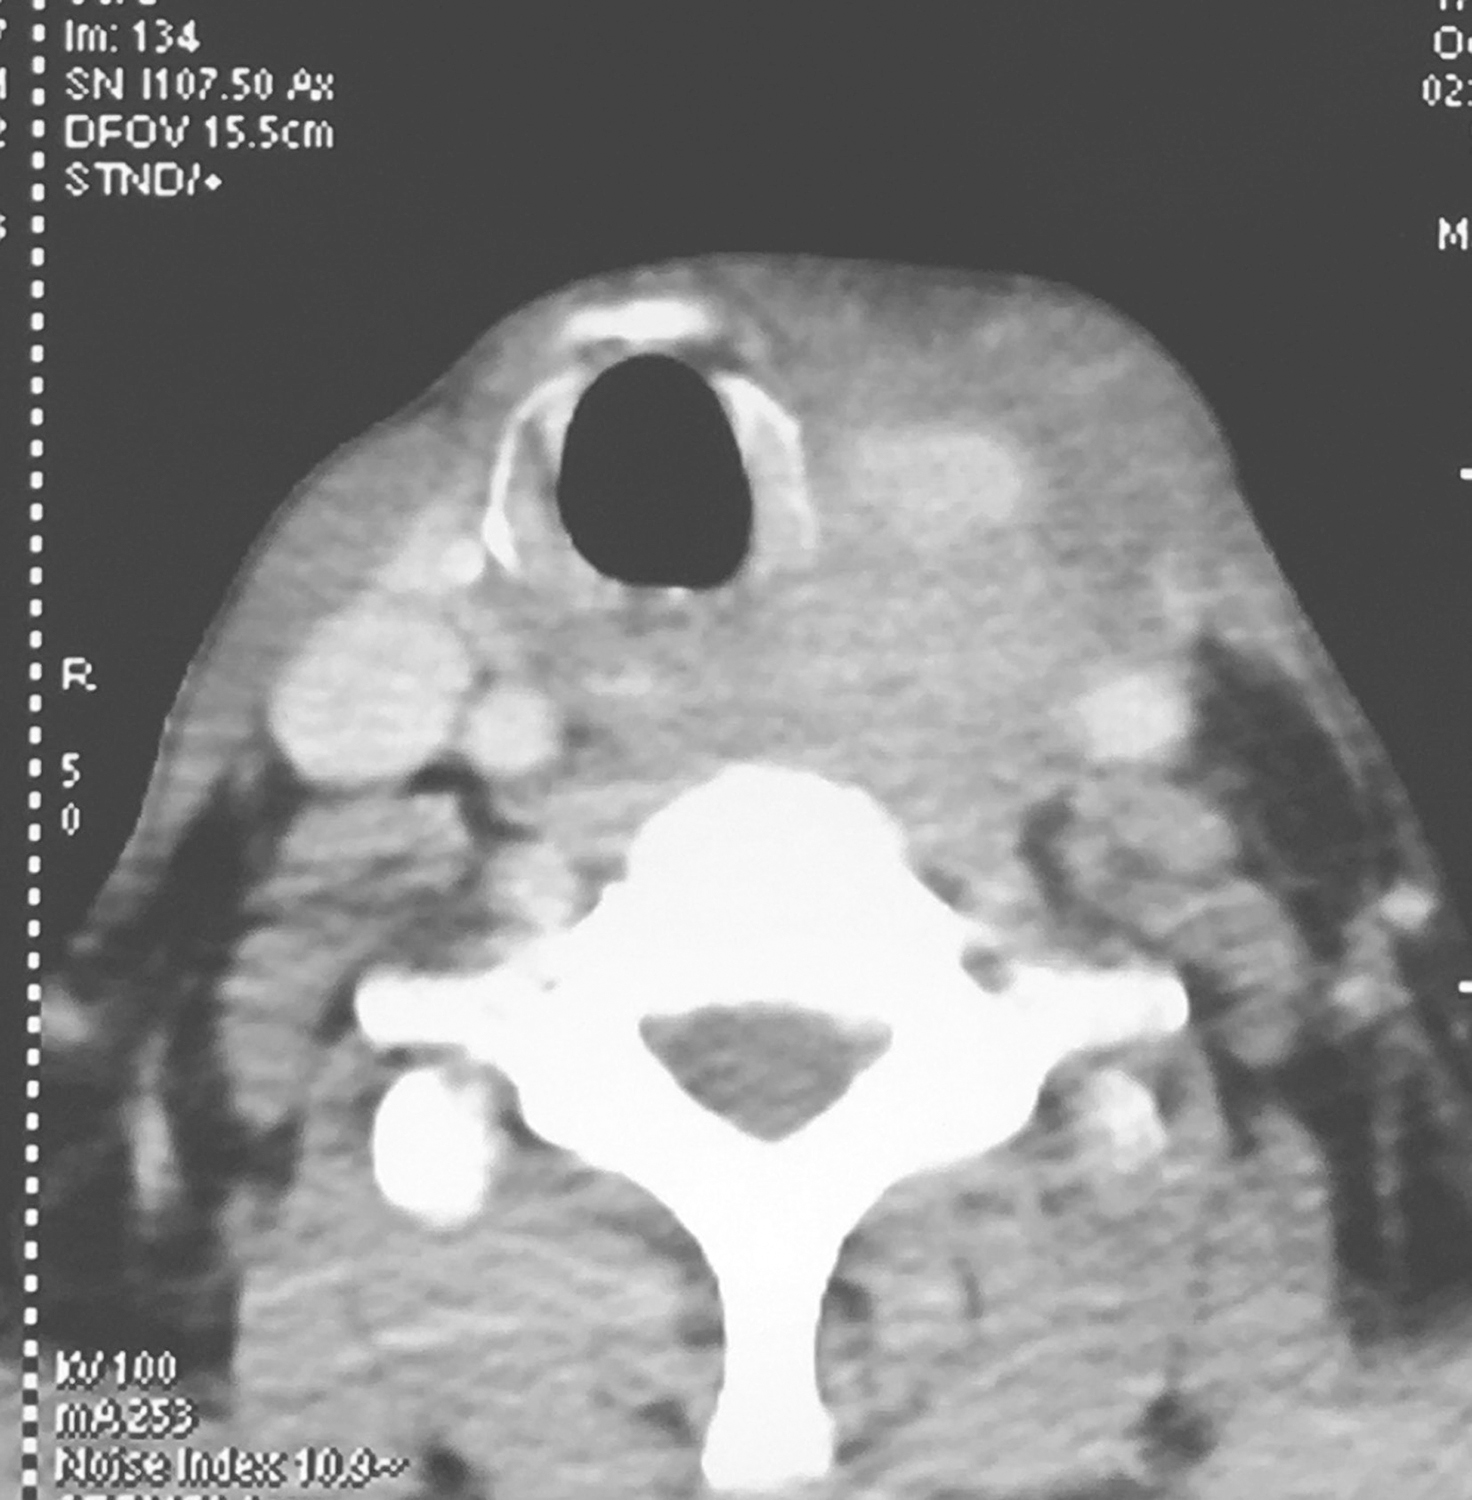

①下咽部左梨状窝区可见软组织密度影,增强扫描可强化,向内累及左侧半喉,侵犯会厌前间隙、声门旁间隙,肿瘤侵透甲状软骨板、舌骨、累及咽侧壁及下咽后壁(图1、图2),向下累及环后区及颈段食管,向外侵犯喉外肌肉及颈前软组织。颈动脉鞘周围多枚肿大淋巴结,部分融合,边界不清,与咽喉肿瘤及颈前肌肉融合,右侧甲状腺受侵(图3),颈内静脉闭塞(图4),颈总动脉与肿瘤边界不清。右侧颈鞘周围也可见多枚肿大淋巴结,增强扫描可见强化。②双肺纹理增粗,双肺野及纵隔内未见异常。

影像学诊断:符合下咽部恶性肿瘤累及喉,双颈部多发淋巴结转移表现。

图3颈胸部增强CT示颈动脉鞘周围多枚肿大淋巴结

图4颈胸部增强CT示颈内静脉闭塞